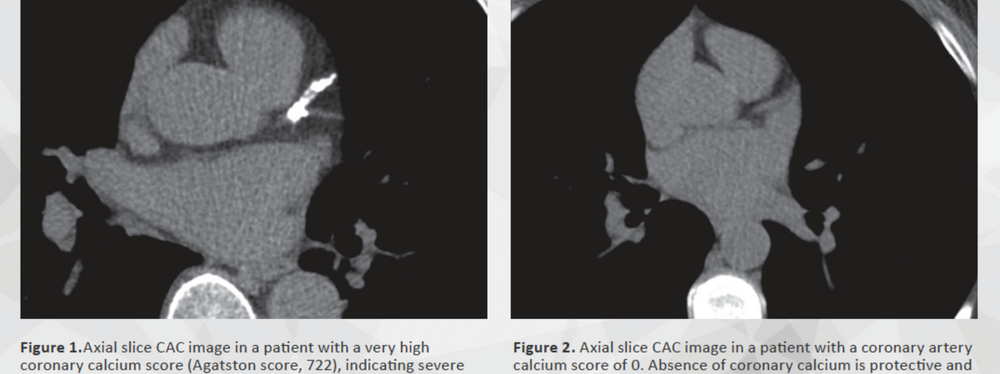

A coronary calcium scan is a CT scan of your heart. During the scan, around 50 parallel slices of your chest are obtained by the CT scanner, enabling us to “see” whether calcium is building up in your heart arteries. While calcium itself is not dangerous, it likes to hang out with plaque deposits. And plaque is bad news for your heart. Doctors scan for calcium deposits in heart arteries because they’re really easy to detect with a CT scan (they look bright white, while the heart itself looks grey), and because calcium usually starts to accumulate way before significant blockages develop. So coronary calcium scans are great for detecting coronary artery disease very early – way before a stress test would signal a problem.

When you have a coronary calcium test, a computer program analyzes the images obtained during the scan and comes up with a “calcium score”. The more calcium has deposited in your arteries, the higher your score. As we get older, the chance that some calcium is detected goes up and based upon hundreds of thousands of patients who have had this test done, we know what score to expect given your age and gender.

Back to the calcium score. It’s probably the only time in your life you want to be a zero. A zero score means that no calcified plaque was identified and (based upon multiple studies) that your risk of having a heart attack, or needing a stent or bypass surgery is extremely low -- now, and for the next few years. So low, in fact, that putting you on a statin would be unlikely to make that risk any lower, even if the drug made your cholesterol numbers look better.